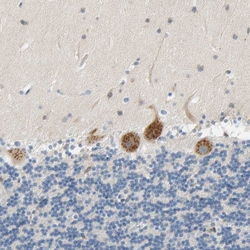

Immunogen sequence: FQSNRMDDQR CCLQEKNCHT ASTTTSSTPP KMMLKTSSVP VVSPNTDEFL DLLASSQSRR LDDQRASFSN LPGLRLTQNS QSVLSHLMTN DNKEADEDFF D Highest antigen sequence identity to the following orthologs: Mouse - 78%, Rat - 75%.

The protein encoded by this gene belongs to a family of proteins that modulate activation of G proteins, which transduce extracellular signals received by cell surface receptors into integrated cellular responses. The N-terminal half of this protein contains 10 copies of leu-gly-asn repeat, and the C-terminal half contains 4 GoLoco motifs, which are involved in guanine nucleotide exchange. This protein may play a role in neuroblast division and in the development of normal hearing. Mutations in this gene are associated with autosomal recessive nonsyndromic deafness.

| Applications | Immunohistochemistry (Paraffin), Western Blot |